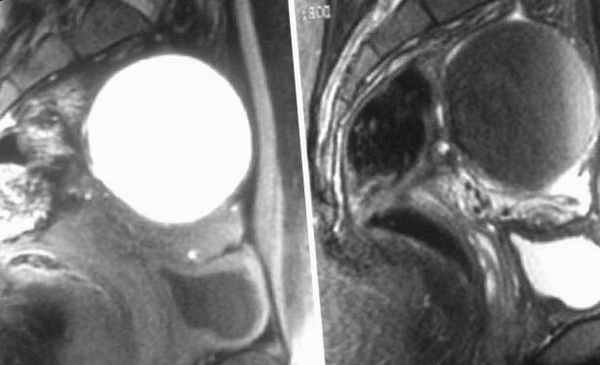

Киста желтого тела яичника — это доброкачественное образование в ткани левого либо правого яичника. Она формируется из желтого тела, которое не подверглось регрессии. Из-за сбоя в системе кровообращения в женской половой железе скапливается жидкость геморрагического либо серозного характера. Если изучить фото кисты, можно увидеть овальное образование, стенки которого уплотнены зернистыми лютеиновыми клетками.

Также различают однокамерные и многокамерные кисты. Однокамерные кисты имеют всего одну полость (камеру, мешок), заполненную жидкостью, а многокамерные – несколько. В основном лютеиновые кисты небольших (до 5 см), реже средних размеров (до 6-8 см), однокамерные, односторонние, с утолщенной стенкой, состоящей из фиброзной ткани и клеток желтого тела. Полость кистозного образования преимущественно заполнена серозной жидкостью желтоватого цвета, иногда с примесью крови.

На следующем этапе проводится динамическое УЗИ органов брюшной полости и малого таза. Стоит помнить, что УЗИ желательно делать в первой половине менструального цикла.

В сложных случаях, для уточнения диагноза или с целью дифференциации лютеиновой кисты от кистомы, текалютеинового ретенционного образования, опухолей яичника может понадобиться диагностическое лапароскопическое исследование.